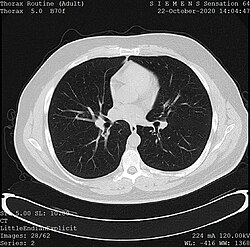

One frame of a CT scan of the chest showing the heart and lungs